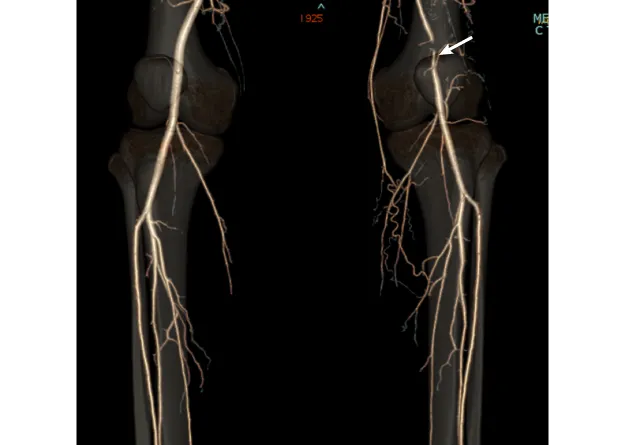

図1

図1. 右膝窩動脈瘤

• 【血管造影所見】膝窩動脈瘤(矢印)

• 【治療】膝窩動脈瘤切除、自家静脈置換術(矢印)